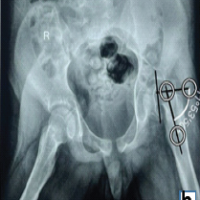

During the patient’s next follow-up visit, 1 month later, the patient complained of palpable hardware around his right knee. Repeat radiographs revealed a hypertrophic non-union with proximal migration of the nail and loosening of the distal interlocking screws (Fig. 5). He was initially treated conservatively; however, symptoms persisted for over 2 months. He then underwent removal of the right distal interlocking screws, augmentation with plate and screw fixation, and revision of the proximal interlocking screws. In a subsequent follow-up 3 weeks later, the patient noted a palpable mass around his left distal thigh. In addition, he developed a sacral decubitus ulcer that required referral to outpatient wound care. Conservative treatment with repeat imaging in 2 months was planned; however, the patient was lost to follow-up. The patient presented to the clinic 1 year later with complaints of palpable distal thigh masses bilaterally and feelings of heaviness in his legs. Radiographs revealed bilateral fracture healing with heterotopic ossification on the left, a well-fixed distal femur plate on the right, and no hardware failure (Fig. 6 and 7). The prominent left-sided heterotopic ossification and palpable right-sided distal femur plate caused significant discomfort. These complications greatly decreased his quality of life and caused him extreme distress. He was referred to a tertiary center for a second opinion, where radiographs revealed bilaterally healed distal femur fractures (Fig. 8 and 9). Removal of the right distal femur plate, left intramedullary nail, and left TTC nail was recommended to improve his quality of life. Unfortunately, the patient passed away from causes indirectly related to his orthopedic injuries before any further follow-up or surgical interventions could take place.